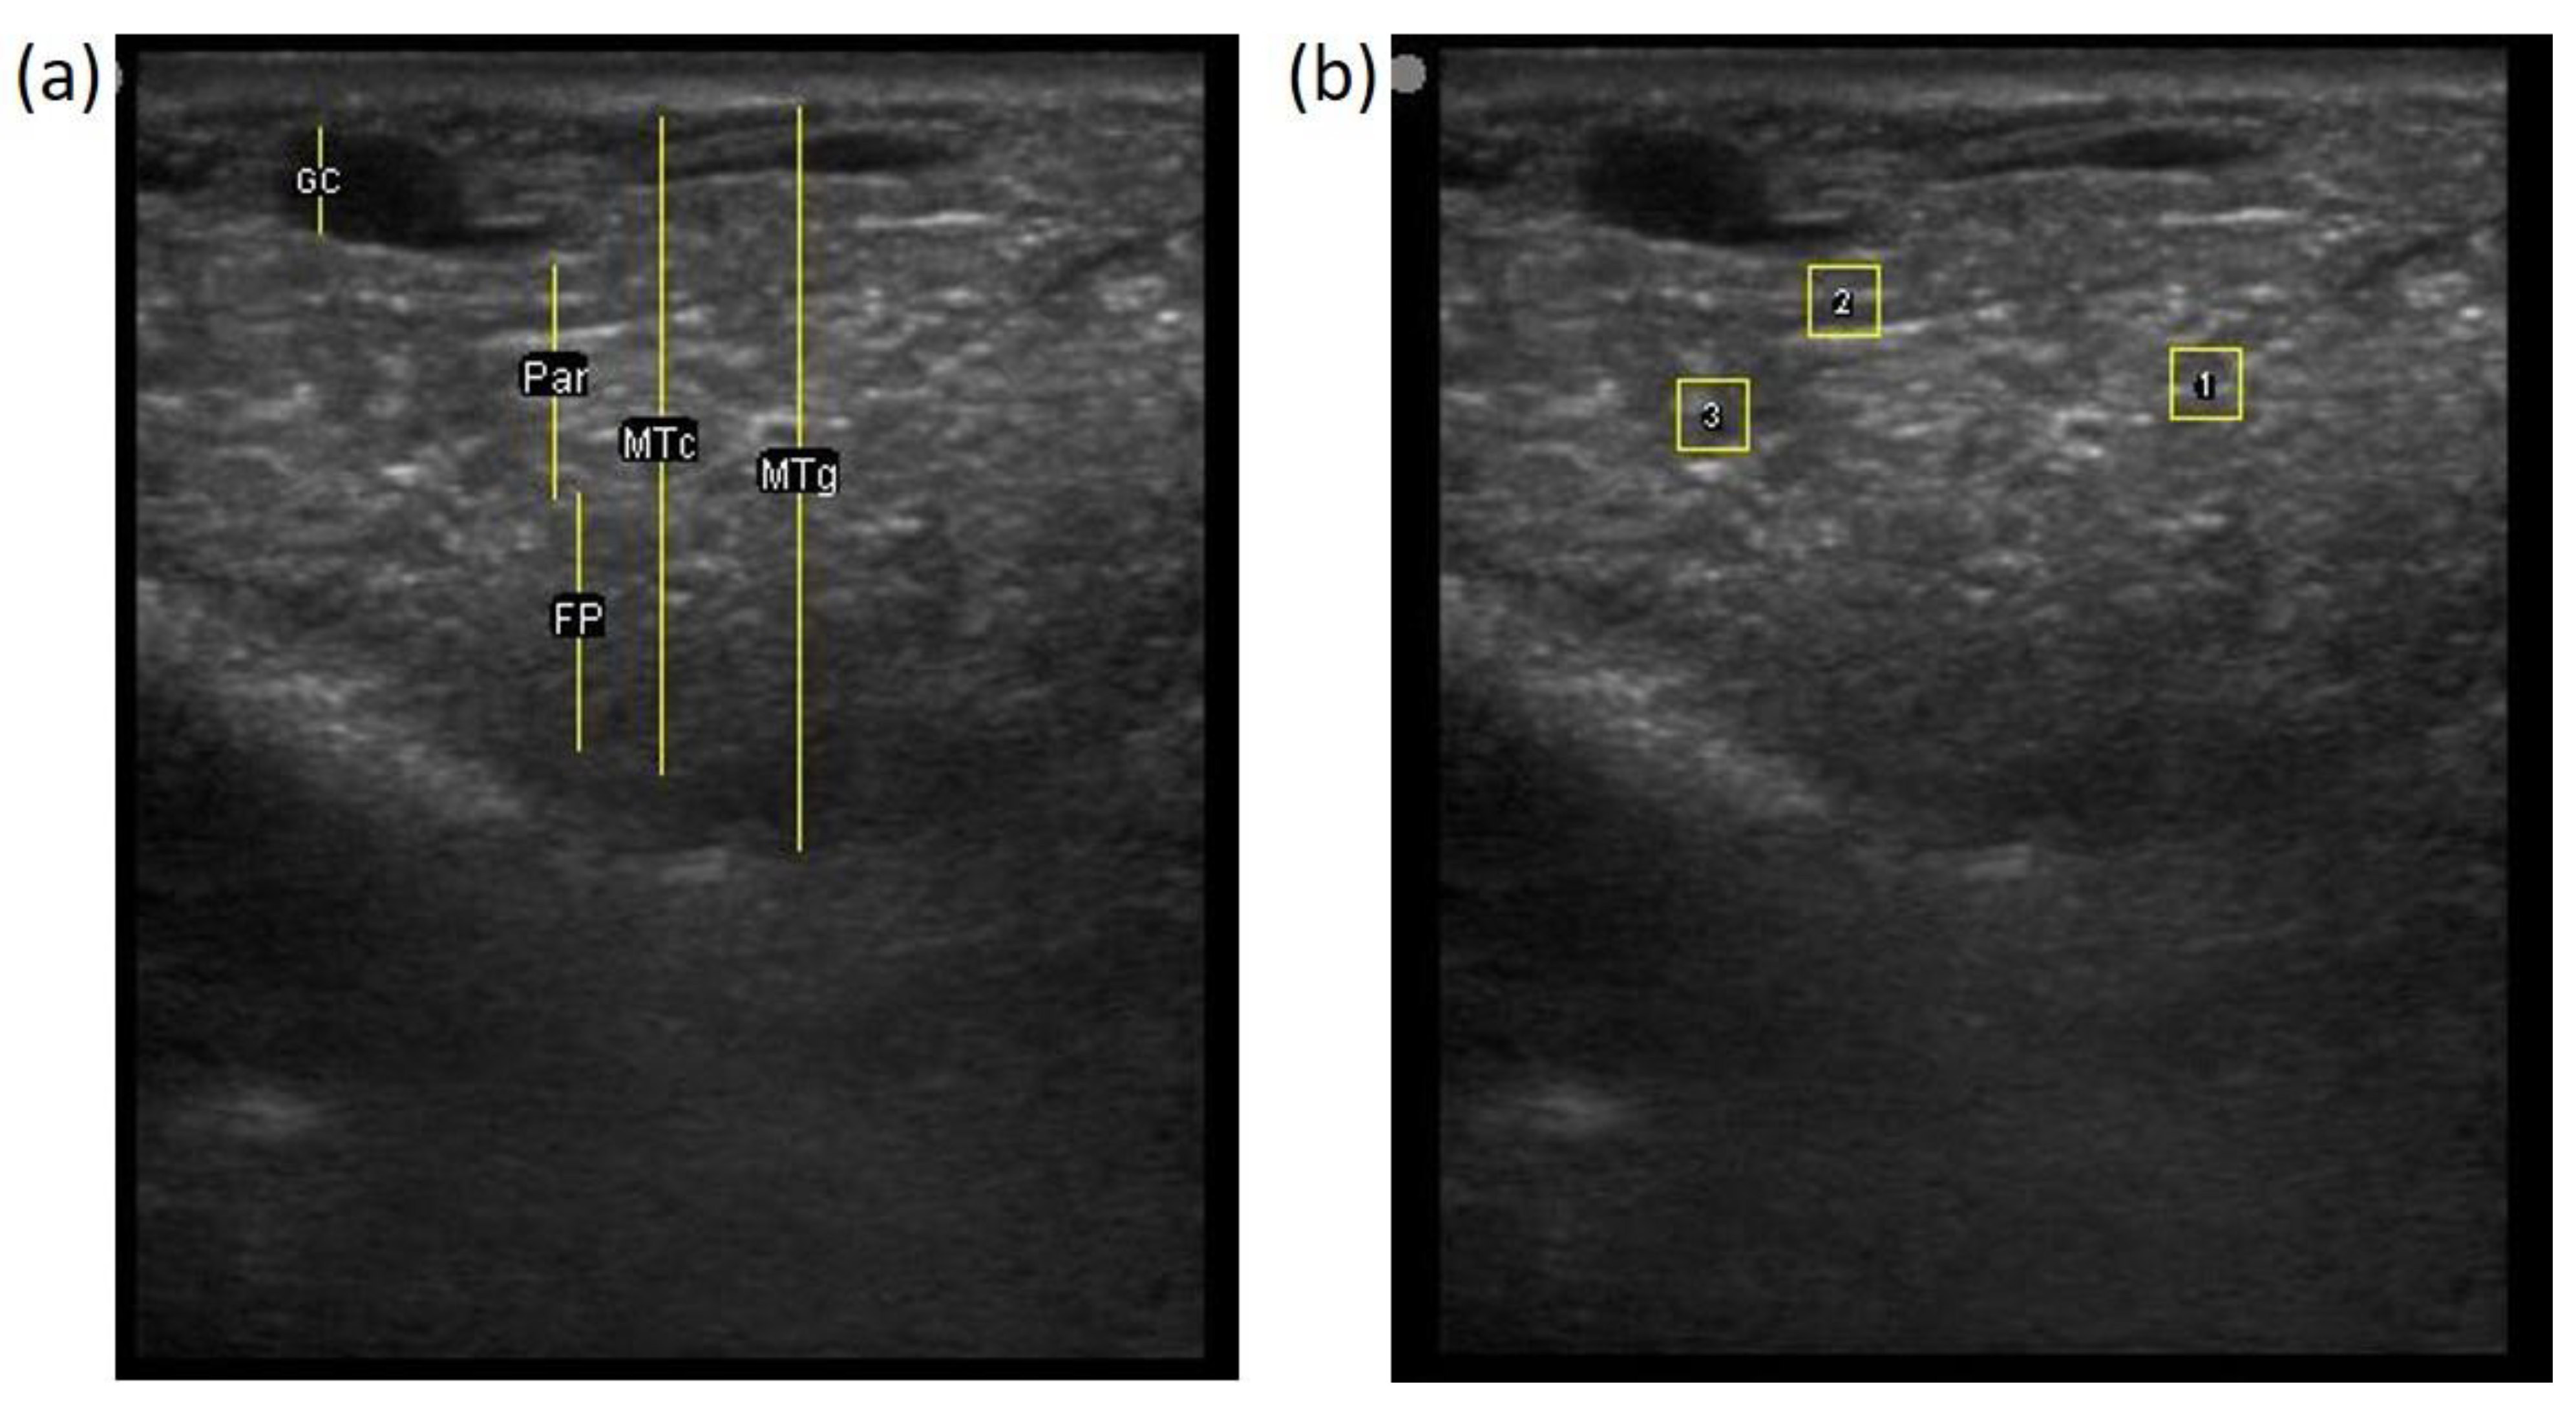

The image processing was undertaken using ImageJ software [28] as used by Abràmoff et al. [29]. The scales between pixels and millimetres were calculated based on the number of pixels, the scanning depth (mm), and the transducer width (mm) (Figure 4). This method relies on the ability of the operator to interpret and identify lines on the images. To standardize the assessment compartment depth, drawing templates were created for each time point as used by Molenaar et al. [30] and included four representative images from four different yearling ewes with and without the lines drawn for each compartment (Appendix A). The total depth of mammary gland conservative (MTc) was the smallest likely demarcation (abdominal wall) of the mammary gland (Figure 5a), and total depth of the mammary gland generous (MTg) was the largest likely demarcation of the mammary gland visible on the image [30] (Figure 5a). The MTc, MTg, fat pad (FP), parenchyma (PAR), and gland cistern (GC) depths were estimated at the deepest point for each sub-compartment, excluding the skin layers, using the straight tracer (Figure 5a) and were expressed in millimetres.

Figure 5.

(a) Demonstration of delimitations of the mammary total depth conservative (MTc) and generous (MTg), mammary gland cistern (GC), parenchyma (PAR) and the fat pad (FP) and (b) Demonstration of randomly positioning of regions of interest (1, 2, 3) in the parenchyma.

To assess the development of the parenchyma at P107, L29, and L100, three regions of interest (ROI; [26]) were randomly drawn in the parenchyma area, each square measured 6.7 mm2 (Figure 5b). The brightness of each pixel corresponded to echogenicity and was numerically represented on a scale of 256 levels of grey [31]. Echogenicity is defined as the capacity of tissues to interact and reflect the sound waves of the transducer [32]. This capacity varies with tissues, i.e., liquids have very low echogenicity [32] and fat has greater echogenicity but attenuates as the depth increases [30].